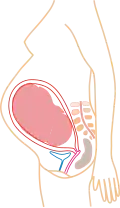

Относительный размер в 1-м месяце (упрощенное изображение)

Относительный размер в 3-м месяце (упрощенное изображение)

Относительный размер в 5-м месяце (упрощенное изображение)

Относительный размер в 9-м месяце (упрощенное изображение)